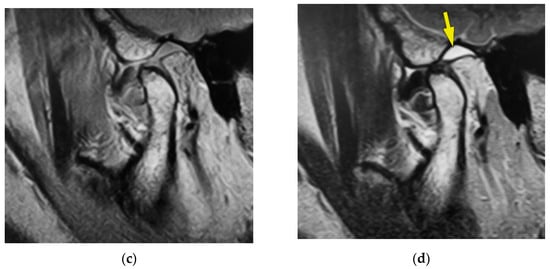

The symptom proportion results are shown in Figure 2. In the cross-tabulation, the proportion of disc displacement (88.5%) was significantly larger than that of normal disc placement (11.5%) (χ2(1) = 77.87, p < 0.01), and the deformation of the disc (59.5%) was significantly more frequent than normal disc formation (40.5%) (χ2(1) = 4.77, p < 0.05). Bone deformation (38.2%) was significantly less frequent than normal bone formation (61.8%) (χ2(1) = 24.80, p < 0.01), and the proportion of joint effusion (28.2%) was significantly smaller than that without joint effusion (71.8%) (χ2(1) = 7.34, p < 0.01). The other symptoms and observations, such as myofascial pain, arthralgia, mouth-opening disturbance, and disc displacement without reduction, were found in about half of the TMJs in this study.

Figure 2.

Proportion of symptom and observations.